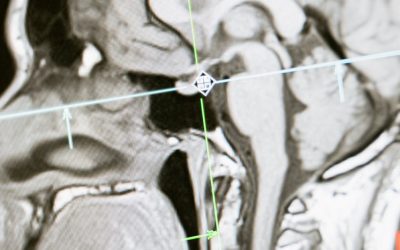

Ғалымдар ұйқы қанбаудың қауіпті салдарын анықтады. Бұл кезде мидағы сұйықтық айналымы бұзылып, ми жұмысы уақытша тоқтап қалады екен.